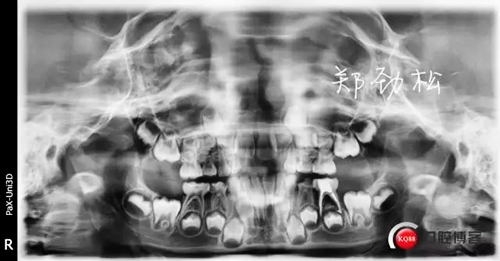

我的病例二 8E深齲導致的根尖炎

常規(guī)的開髓擴根后vitapex糊劑充填,可見近中根有明顯的糊劑超充。

一月后永久充填復查時可見炎癥明顯好轉,近中根超充的糊劑也吸收了,臨床癥狀也消失了。